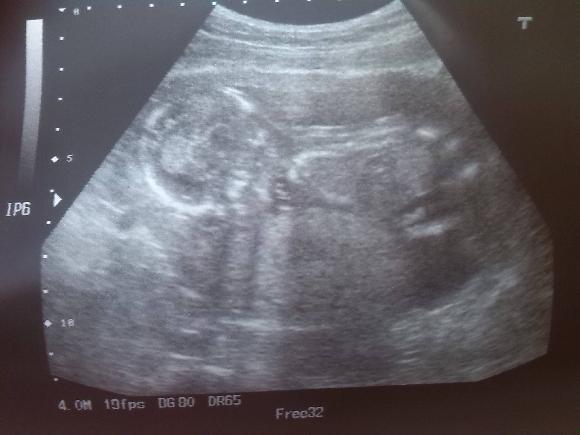

dokladam fotecku zlaticka

Lůco a Brozanko, gratuluji k výborným výsledkům a Brozanko, co se týče toho utz tak já osobně bych to viděla na holčičku. Pindík tam vidět fakt nebyl. Mám naštudováno hodně ultrazvuků z youtube, tak vím, že u kluků je ten pindík opravdu nepřehlídnutelný